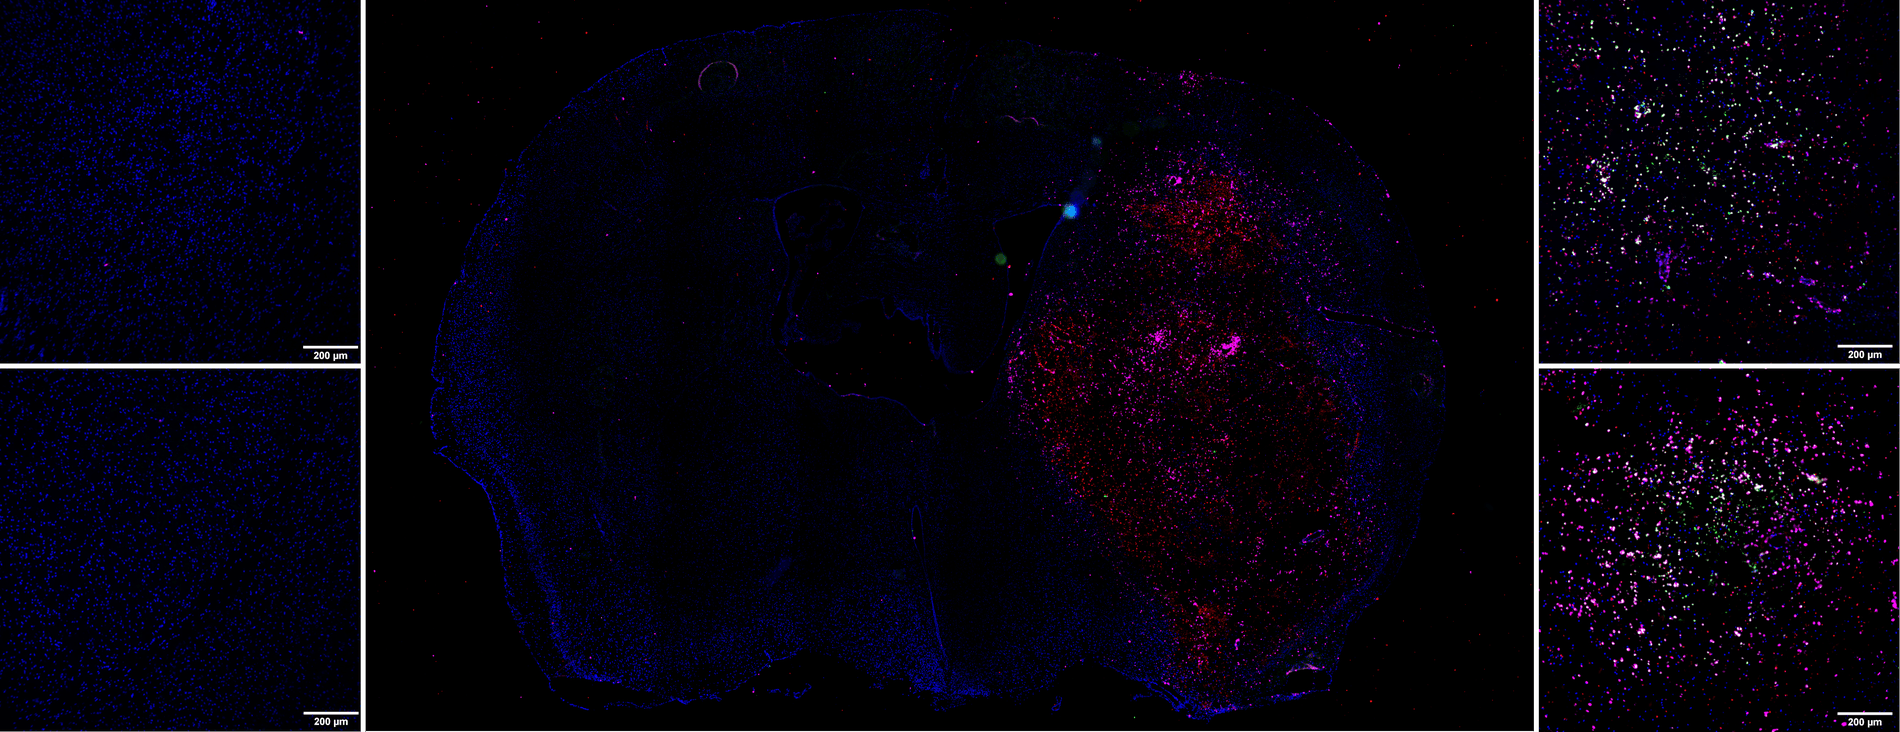

This molecular imaging data can be supplemented by immunohistochemistry studies. Following tissue sampling, we can, for example, quantify:

- The activation of neutrophiles, macrophages/monocytes and microglial cells via an anti-MPO antibody

- The implementation of Neutrophil Extracellular Traps (NETs) via the Anti-H3Cit antibody

- The presence of neutrophiles via the Anti-Ly-6G antibody